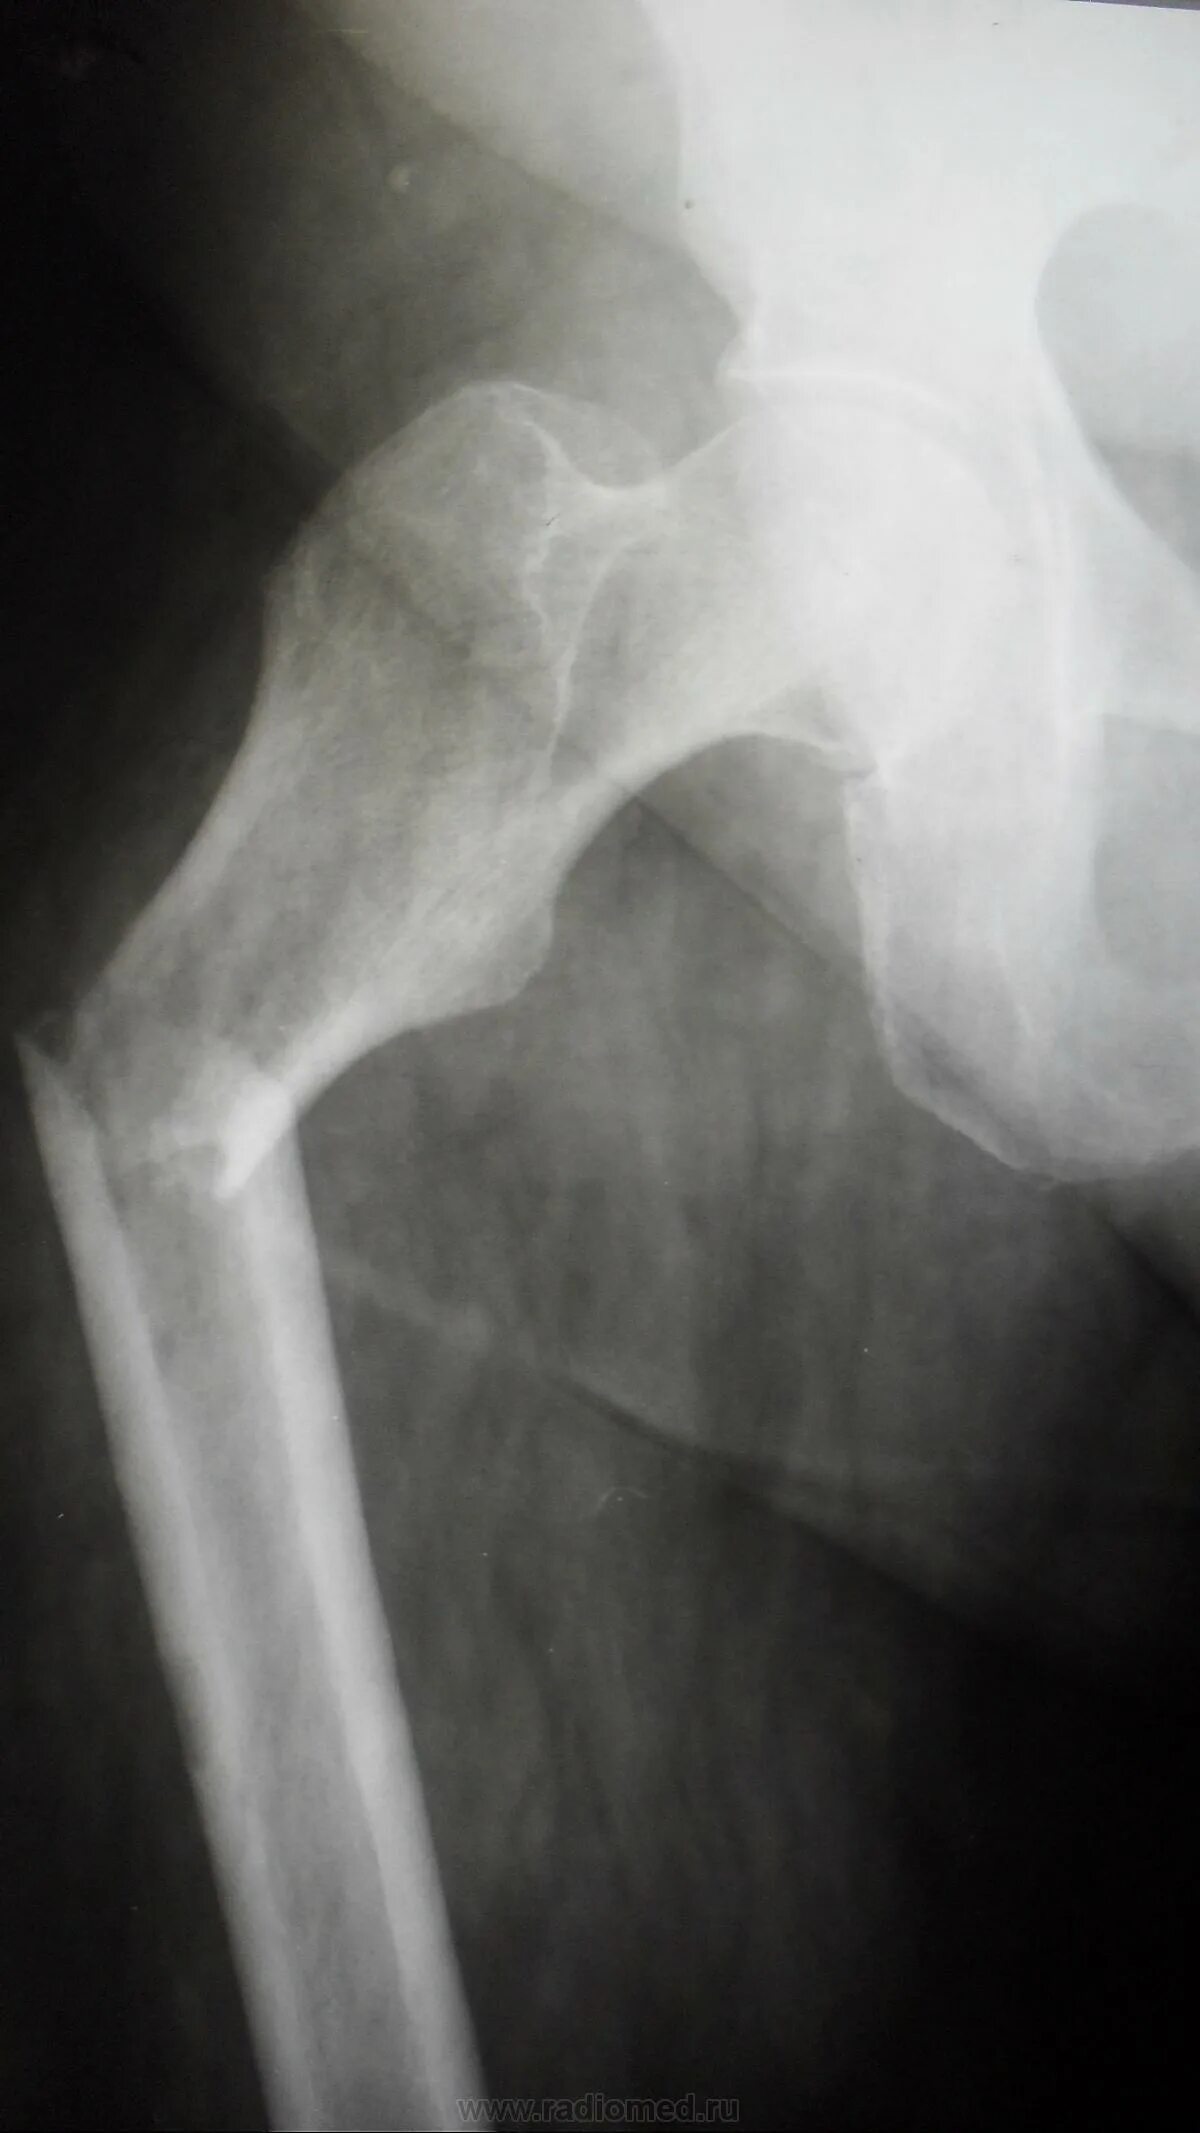

Патологический перелом бедра